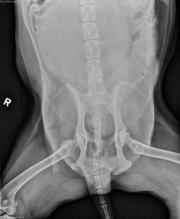

This week’s case is a 12-year-old male neutered Labrador Retriever who is straining to urinate and defecate. Hypercalcemia was noted on serum biochemistry. Where is the abnormality?

There is a large, lobular, soft tissue opacity mass in the caudal retroperitoneal space. The colon is displaced ventrally, and is distended with fecal material. The bladder is enlarged and cranially displaced. The peritoneal detail is good. The liver, spleen, and kidneys are normal in size and shape. No abnormalities are noted in the stomach or small intestine. There is spondylosis deformans at the lumbosacral space.

Sublumbar lymphadenopathy – metastatic disease from pelvic neoplasia, lymphoma

Metastatic anal sac adenocarcinoma